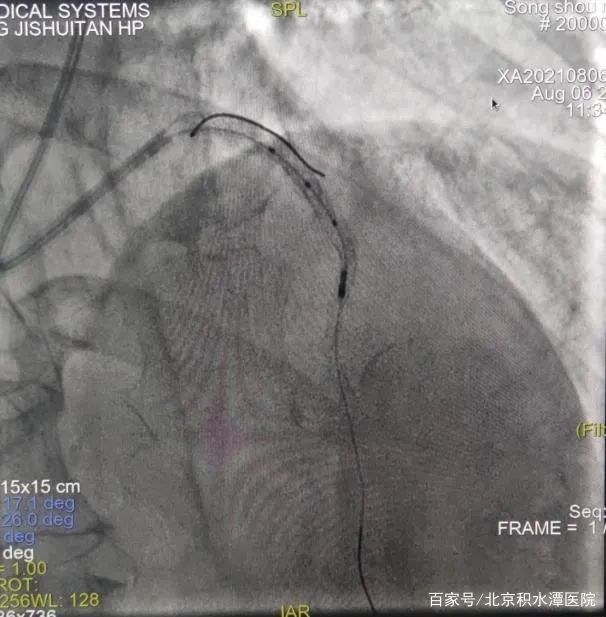

但在上台后,发现3个月过后,左前降支血管已经完全闭塞,手术难度远远超出预期,无法判断血管走行和方向。所以决定采用微量造影剂的办法进行介入治疗。刘教授凭借经验,在只应用少许造影剂的情况下,不断更换导丝进行尝试后,终于通过闭塞病变到达血管远端。导丝通过闭塞病变后,不再使用造影剂,使用IVUS检查发现,闭塞处有严重钙化斑块。通过IVUS明确支架植入位置和大小,最终成功植入支架。手术过程共使用造影剂约20ml。术后监测患者血肌酐,无明显改变并且处于稳定状态。患者也高高兴兴地出院了。

在对李女士的治疗过程中,刘巍教授在患者的第一次冠状动脉造影的影像指导下,经过远端桡动脉入路,将指引导管放置在右侧冠状动脉开口,导丝送至血管远端,但是由于患者病变弥漫,狭窄严重,并且开口就有病变,指引导管稍微深插就会出现压力下降和心电图ST段抬高,手术的难度超出预期。这时使用IVUS进行血管内超声检查,结果显示,右冠状动脉中段最小管腔面积仅2.0mm2,并且可见超声衰减斑块和高负荷脂质斑块,并且病变比预想的还要弥漫和严重。刘教授团队根据边支定位以及IVUS导管标记点定位,对狭窄病变进行充分预扩张,复查IVUS提示扩张效果满意后,根据IVUS定位精准地植入了两枚支架,再次复查IVUS提示支架膨胀及贴壁良好,无边缘夹层等情况。手术过程顺利,全程未使用一滴造影剂就成功完成了支架的植入。术后患者没有出现任何不适。手术过程不到30分钟,患者术后症状立刻缓解。第3天就出院了。

但在上台后,发现3个月过后,左前降支血管已经完全闭塞,手术难度远远超出预期,无法判断血管走行和方向。所以决定采用微量造影剂的办法进行介入治疗。刘教授凭借经验,在只应用少许造影剂的情况下,不断更换导丝进行尝试后,终于通过闭塞病变到达血管远端。导丝通过闭塞病变后,不再使用造影剂,使用IVUS检查发现,闭塞处有严重钙化斑块。通过IVUS明确支架植入位置和大小,最终成功植入支架。手术过程共使用造影剂约20ml。术后监测患者血肌酐,无明显改变并且处于稳定状态。患者也高高兴兴地出院了。